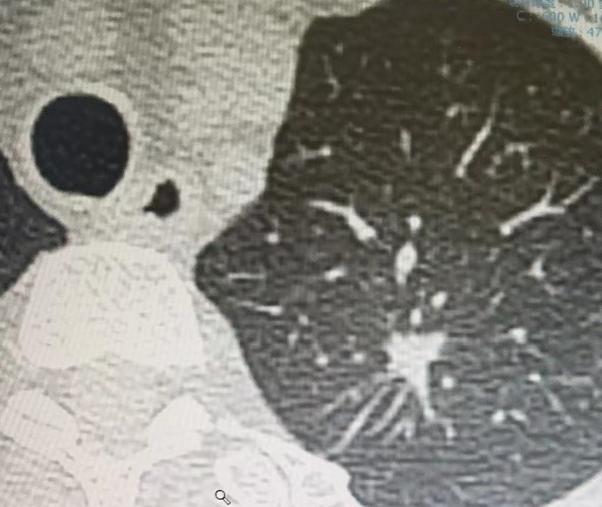

肺结核患者在拍CT、照片时,肺部也可能出现结节样表现。我们生活的空气中存在各种细菌,而肺结核是由结核杆菌通过飞沫传播的疾病。 具体来说,人群中如果有结核患者,他在呼吸、咳嗽、打喷嚏时,口腔和鼻孔会喷出飞沫,这些飞沫中就含有结核杆菌。 如果此时你恰好就在他身边,吸入了含有结核杆菌的空气,且自身免疫力较低,结核杆菌就可能在你的肺部形成结核病灶。随着细菌在肺部繁殖,就会呈现出结节样的表现。 肺结核的病情发展因人而异:如果感染的结核杆菌数量少、毒性低,人体自身的免疫力完全可以实现自愈; 但如果自身无法控制病情,症状逐渐加重,就必须及时前往医院就诊。尤其是出现明显症状,或检查发现肺部病灶较大时,一定要到专业医院进行准确诊断和规范治疗。 需要注意的是,结核杆菌不仅会感染肺部,还可能侵犯身体其他部位,比如骨头、脑部以及其他脏器。 但由于结核杆菌主要通过空气传播,因此肺部是最常被感染的部位,也是感染后的首要发病部位。 肺部感染结核杆菌后,往往会出现一些典型症状,出现这些症状时一定要提高警惕: 1、呼吸道症状,比如持续不愈的咳嗽、咳痰。普通的上呼吸道感染、气管炎,通常过几天就会逐渐缓解,但如果咳嗽、咳痰持续不见好转,甚至咳出黄色浓痰,往往提示存在炎症,需警惕肺结核的可能。 2、全身中毒症状,主要有三个表现:一是疲劳乏力,总是感觉没力气、浑身酸痛; 二是不明原因的低热,体温常维持在37℃多,持续不退; 三是盗汗,也就是在夜间睡眠时出虚汗,通常半夜醒来会发现头部、身上布满汗水。此外,睡眠不佳、食欲减退等,也属于结核中毒的常见表现。 如果出现以上这些症状,同时CT、胸片检查发现肺部有结节或病灶,一定要及时到医院验血、做皮试,排查是否感染肺结核。[谢谢][玫瑰]